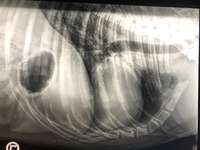

Unser Rumänien-Import hat Rickettsien mitgebracht. Nun bekommet er seit 3 Tagen Doxy.